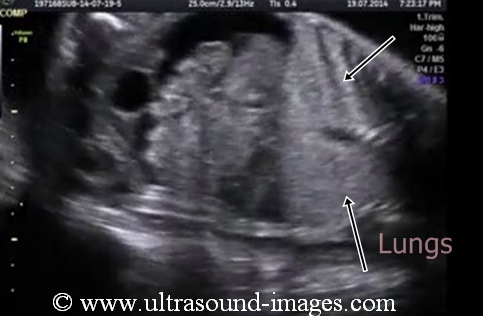

This is yet another example of Fetal hydrothorax, which is the term used for pleural effusion in the fetus. In this case there is a large pleural effusion or hydrothorax affecting the right lung. Unilateral hydrothorax usually involves the right side. This second trimester fetus shows the pleural effusion or hydrothorax completely encircling the fetal right lung. in this case the large right hydrothorax appears to have caused a complete collapse of the right lung. Such a large hydrothorax if present at birth can be life-threatening. The fluid usually contains chyle.

This ultrasound image is courtesy of Dr Durr-e-Sabih, FRCP.